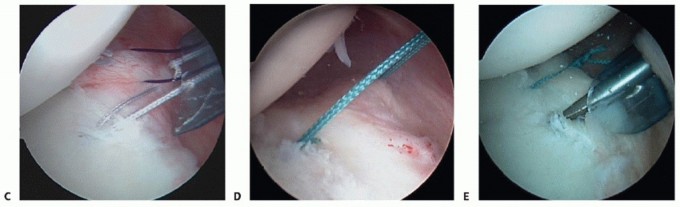

TECH FIG 1 • A. Probe entering the posterior cannula is demonstrating mobility of posterior Bankart lesion with evidence of granulation tissue in the defect. B. After the lesion is defined, a Liberator knife is introduced to take down the fibrous interface in the posterior Bankart lesion. C. After preparation using a high-speed burr, the posterior inferior aspect of the glenoid is lightly decorticated in preparation for anchor placement. D. Initial anchor placement begins at the inferior extent of the glenoid with the use of a guide. E. First anchor in place 2 mm up on the articular surface.

This position allows secure placement of an anchor while allowing optimal inferior capsular plication. Bioabsorbable anchors are employed for this reconstruction (TECH FIG 1E).

Suturing

A Spectrum 45-degree-offset suture passer, preloaded with a no. 0 polydioxanone (PDS) monofilament suture (Ethicon, Somerville, NJ), is passed through the posterior cannula, capturing the inferior capsule in the area of the posterior band of the IGHL (TECH FIG 2A).

This tissue is brought superiorly and the second pass comes deep, exiting at the posterior labral defect.

TECH FIG 2 • A. The Spectrum suture passer is used to capture inferior capsular tissue and the posterior band of the IGHL. B. After anchor placement, stability is assessed with gentle traction on the anchor sutures and a monofilament suture is passed through the suture passer. (continued)

The PDS suture is reeled into the joint through the passer and retrieved in the posterior cannula using a ring grasper (TECH FIG 2B,C).

The deep limb of the PDS is tied to one limb of the anchor suture, and using a pulling technique, the PDS is drawn in a retrograde fashion, with the anchor suture attached, through the capsule and labral tissue, thereby creating a simple stitch (TECH FIG 2D*).

This allows the inferior capsule to be drawn superiorly and medially while at the same time closing the posterior Bankart lesion.

TECH FIG 2 • (continued) C. The monofilament suture, having been passed through a capsule inferiorly, is drawn up to assess capsular mobility and determine the amount of translation. D. One limb of the anchor suture is tied to the monofilament suture, which is then drawn back out the posterior cannula, thus creating a simple stitch. E. Having tied the suture on the first anchor, a drill hole is created 7 to 8 mm superiorly for the second anchor. F. A second anchor suture has been passed, demonstrating the purchase of additional posterior capsule. G. With the final superior anchor in position, the suture passer is directed superiorly to capture additional posteromedial capsule and superior labrum. H. Final anchor sutures are tied, demonstrating excellent reconstruction of the posterolabral defect, recreating the posterior labrum bumper effect.

A second suture is placed after tying the first suture in a similar fashion, again incorporating the capsule as well as labrum (TECH FIG 2E,F).

This process is repeated as many times as is necessary, moving superiorly at 6- to 8-mm increments, thereby obliterating any labral defect and capsular redundancy (TECH FIG 2G,H).